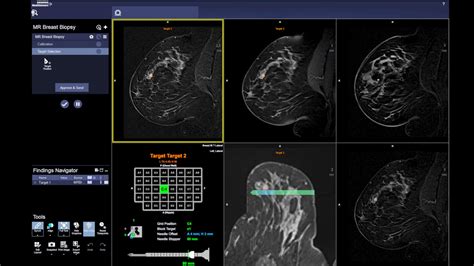

Breast MRI with dye, also known as contrast-enhanced breast MRI, is a powerful diagnostic tool used to detect and evaluate breast abnormalities. This advanced imaging technique provides detailed images of the breast tissue, helping healthcare professionals to identify and diagnose conditions such as breast cancer, fibrocystic changes, and other breast diseases. Unlike traditional mammography, which uses X-rays, breast MRI with dye utilizes magnetic fields and radio waves to produce high-resolution images. The contrast dye enhances the visibility of blood vessels and tissues, making it easier to detect abnormalities that might be missed with other imaging methods.

Breast MRI with dye is particularly useful for women who have dense breast tissue, a family history of breast cancer, or who are at high risk due to genetic mutations such as BRCA1 or BRCA2. The procedure involves injecting a contrast agent into the bloodstream, which helps to highlight areas of increased blood flow, a common characteristic of tumors. This enhanced visibility allows radiologists to better differentiate between benign and malignant lesions.

Interpreting the results of a breast MRI with dye involves a thorough review of the images by a radiologist. The radiologist will look for abnormalities such as masses, cysts, or areas of increased blood flow that could indicate the presence of a tumor. The results are typically categorized using the Breast Imaging Reporting and Data System (BI-RADS) classification, which ranges from 0 to 6:

If the results indicate a suspicious or malignant finding, further diagnostic tests such as a biopsy may be recommended to confirm the diagnosis. A biopsy involves taking a small sample of tissue from the suspicious area for laboratory analysis.